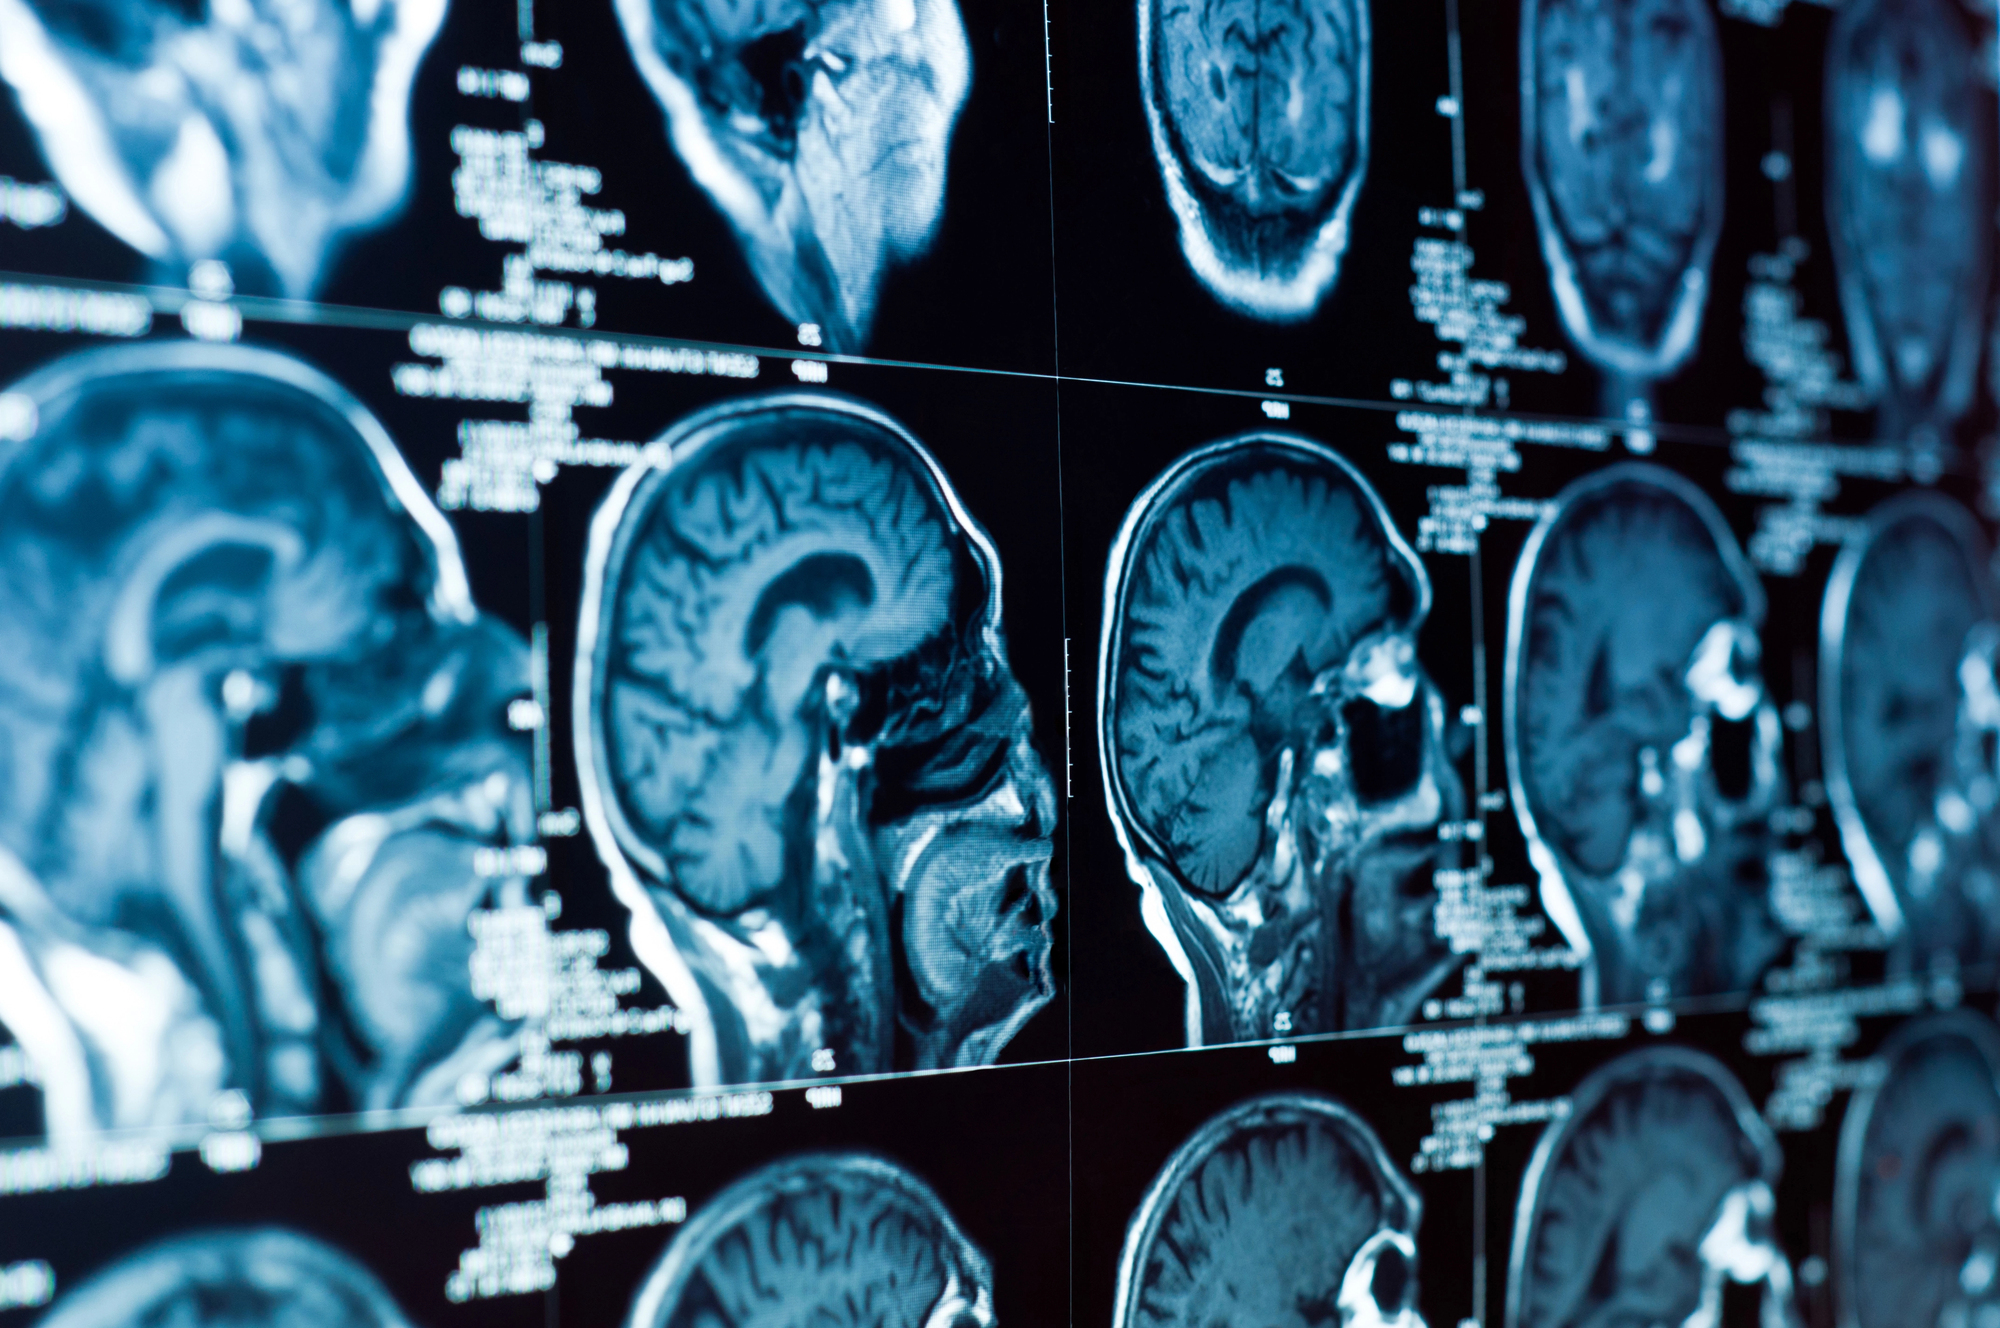

Кожен з шести добровольців провів майже 17 годин всередині апарату МРТ, переглядаючи 2 тис. 180 коротких відео без звуку. Ролики включали грайливих тварин, абстрактну анімацію з глибоким емоційним впливом та повсякденні речі. Кожне відео тривало по кілька секунд, однак разом вони надали широкий набір даних про те, як мозок обробляє візуальний досвід.

Далі вчені порівнювали активність мозку, записану під час кожного відео, з цими семантичними сигнатурами. Тобто, вони навчили ШІ розпізнавати, які нейронні патерни відповідають певним типам змісту. Замість використання глибоких, непрозорих нейромереж дослідники використовували прозорішу лінійну модель. Ця модель могла показати, які області мозку відповідають за ті чи інші види семантичної інформації.